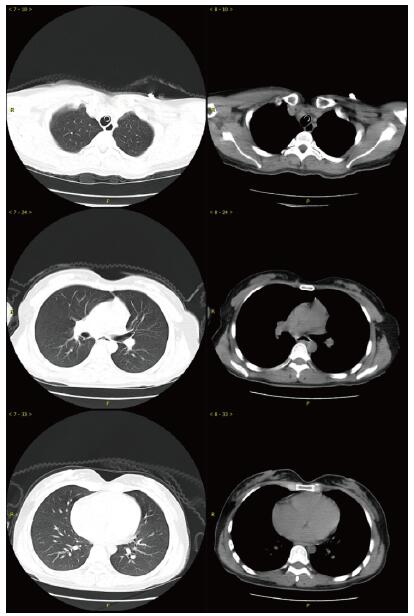

当晚20时到达本院,入院时患者昏迷,血压低、心肌损伤、轻度心衰, 低氧血症, 肝损伤。相关实验室检查:血气PaO2 44 mmHg,生化指标谷丙转氨酶(ALT)528.8 U/L,谷草转氨酶(AST)780.9 U/L,胆红素正常,尿素氮(BUN)3.6 mmol/L,肌酐(Cr)125.7 μmol/L,血糖7.88 mmol/L,心肌肌酐蛋白(cTnT)55.94 ng/mL,N末端B型利钠肽原(NT-pro BNP)495.7 pg/mL,神经元特异性烯醇化酶(NSE)47.46 ng/mL。胸部CT未见明显异常(图 1),头颅CT未见明显异常(图 2A)。给予异甘草酸镁保肝,乙酰半胱氨酸抗氧化,兰索拉唑保护胃黏膜,并予血液灌流治疗一次。

| A:入抢救室当日(中毒首日);B:住院第5天(中毒第6天);C:住院第8天(中毒第9天) 图 2 患者头颅CT影像 |

次日晚间收住入院。住院第2天监测血压99/72 mmHg。实验室检查:cTnT 245.4 ng/L,NT-pro BNP 18.57 pg/mL,BUN 2.68 mmol/L,Cr 40.5 μmol/L,血钾3.82 mmol/L。血气:PO2 116 mmHg,pH 7.498, Lac 1.58 mmol/L。并CRRT治疗:治疗前APTT为32.2 s,阿加曲班抗凝,治疗剂量40 mL/(kg·h)。第3天继续CRRT治疗,阿加曲班抗凝,监测APTT为62.9 s(为正常值2倍)。第4天停CRRT, 记录自发尿量1 920 mL /24 h。第5天神志逐步转清,有指令动作,自主呼吸良好,停机械通气。脱机拔管后查颅脑CT双侧基底节区及脑干低密度影, 考虑中毒性脑病改变(图 2B),胸部CT未见明显异常。监测APTT为26.7 s。第7天患者再次昏迷,并有呼吸急促,脉氧下降。再次行气管插管呼吸机支持。监测肝功能进一步好转(ALT 187.7 U/L,AST 92.2 U/L)。第8天17时发现患者瞳孔不等大,左侧3.5 mm,右侧4.5 mm, 对光反射消失,即查颅脑CT示右侧基底节区出血(图 2C)。家属要求保守治疗。第9天患者处于深昏迷状态,家属放弃继续治疗出院。出院一周后随访患者死亡。

哒螨灵口服中毒后机体细胞内呼吸功能抑制,导致细胞缺氧,无糖酵解,乳酸快速堆积,机体迅速出现代谢性酸中毒,重要脏器灌注不足,早期即可表现肝功能异常甚至肝衰竭;心肌酶谱增高,心肌收缩力减低,胰腺功能受损,血淀粉酶增高,血糖应激性增高[3]。由于人体脑组织供应的血流非常丰富,因此对缺氧表现也非常敏感。但哒螨灵中毒并发脑病报道较少,并发脑出血者罕见。该例患者中毒后出现恶心呕吐,提示该药对胃肠道有刺激性;后出现多系统损伤。早期即出现意识障碍,并渐加重至昏迷,有脑神经元损伤,但早期头颅CT未见明显异常;患者有严重低血压,需要大剂量血管活性药物维持血压;患者严重低氧血症,需要呼吸机支持,但肺部影像学未见明显异常;患者有乳酸酸中毒、肝肾功能损伤和心肌受损,但上述损伤大多在支持治疗2~4 d后完全正常或出现明显好转。但第5天头颅CT提示患者出现中毒性脑病表现,患者神志在短暂好转后又再次恶化,第8天原右侧基底节区水肿部位出现脑出血。